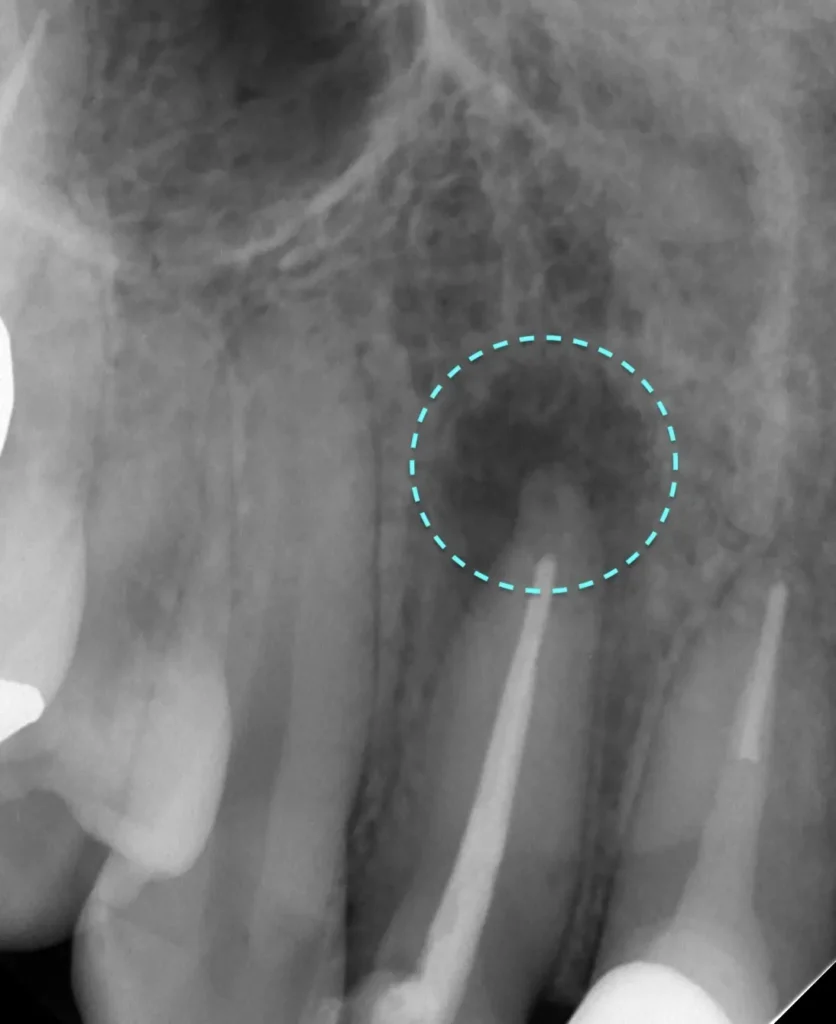

自費根管治療症例2 治療前

左下の奥歯が根の治療を受けているが治らない。

初診時

管の分かれている部分に根の治療による穿孔がありました